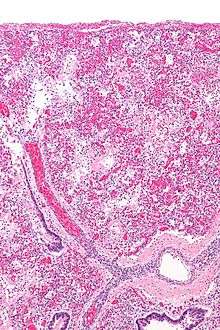

ARDS is a form of noncardiogenic pulmonary edema provoked by an acute injury to the lungs that results in flooding of the lungs' microscopic air sacs responsible for the exchange of gases such as oxygen and carbon dioxide with capillaries in the lungs.[12] Additional common findings in ARDS include partial collapse of the lungs (atelectasis) and low levels of oxygen in the blood (hypoxemia). However, in ARDS, these changes are not due to heart failure. The clinical syndrome is associated with pathological findings including pneumonia, eosinophilic pneumonia, cryptogenic organizing pneumonia, acute fibrinous organizing pneumonia, and diffuse alveolar damage (DAD). Of these, the pathology most commonly associated with ARDS is DAD, which is characterized by a diffuse inflammation of lung tissue. The triggering insult to the tissue usually results in an initial release of chemical signals and other inflammatory mediators secreted by local epithelial and endothelial cells.

Neutrophils and some T-lymphocytes quickly migrate into the inflamed lung tissue and contribute in the amplification of the phenomenon. Typical histological presentation involves diffuse alveolar damage and hyaline membrane formation in alveolar walls. Although the triggering mechanisms are not completely understood, recent research has examined the role of inflammation and mechanical stress.